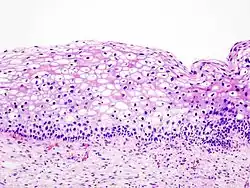

Histologicznie CIN manifestuje się zaburzeniem różnicowania komórek nabłonka wielowarstwowego płaskiego, zmianą morfologii pojedynczych komórek i zaburzeniem budowy architektonicznej całego nabłonka. Komórki prawidłowego nabłonka mają okrągłe, równe jądra o drobnoziarnistej chromatynie rozproszonej regularnie. W nabłonku z cechami neoplazji śródnabłonkowej (CIN) stwierdza się cechy atypii: powiększenie jąder komórkowych, ich hiperchromazję, polimorfizm kształtu, wielkości oraz zabarwienia. Częste są komórki dwu- i wielojądrowe. Organizacja nabłonka jest zaburzona. W miarę nasilenia zmian morfologicznych wzrasta stopień CIN jaki przypisuje się tym zmianom. Ponadto, w komórkach nabłonka zainfekowanego wirusem brodawczaka stwierdza się koilocyty – komórki z dużą jasną wodniczką, silnie zaznaczoną hiperchromazją i charakterystycznym, "pomarszczonym" obrysem. W zainfekowanym HPV nabłonku występuje parakeratoza, a granice międzykomórkowe są wyraźnie widoczne i pogrubiałe. Komórki nabłonka z cechami CIN często "tapetują" cewki gruczołowe, co należy w ocenie histologicznej różnicować z naciekaniem podścieliska.

| CIN I | CIN II | CIN III |

| Proliferacja niedojrzałych komórek ograniczona do dolnej 1/3 nabłonka Zachowana polarność komórek we wszystkich warstwach Nieliczne mitozy u podstawy nabłonka Niewielki polimorfizm jąder komórkowych Może być obecna koilocytoza |

Proliferacja niedojrzałych komórek ograniczona do dolnych 2/3 nabłonka Komórki warstw powierzchownych wykazują cechy dojrzewania obecny polimorfizm jąder komórkowych |

Niedojrzałe komórki na całej wysokości nabłonka Nabłonek pogrubiały, wzrost komórkowości Całkowicie zaburzona architektura nabłonka Liczne, często patologiczne mitozy Nierzadko wybitny polimorfizm jąder komórkowych |